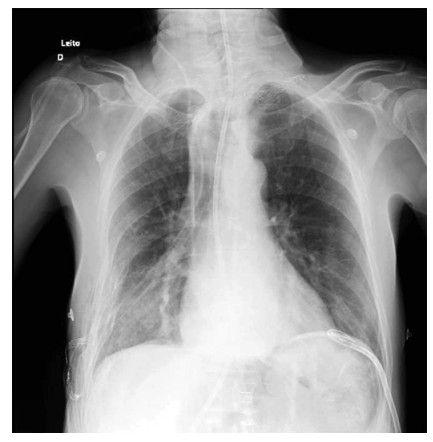

Abstract: Hiatal hernia is a rare postoperative complication of esophagectomy in the treatment of esophageal cancer. Although rare, its incidence increased after the establishment of minimally invasive surgical techniques. The patient is usually oligosymptomatic, and the diagnosis is made in the late postoperative period, during outpatient follow-up. The initial presentation of hiatus hernia with hemodynamic instability is a rare condition that has never been described in the literature before. In the following report, we address the clinical picture, diagnosis, and treatment for this condition, discussing the main nuances of the literature.